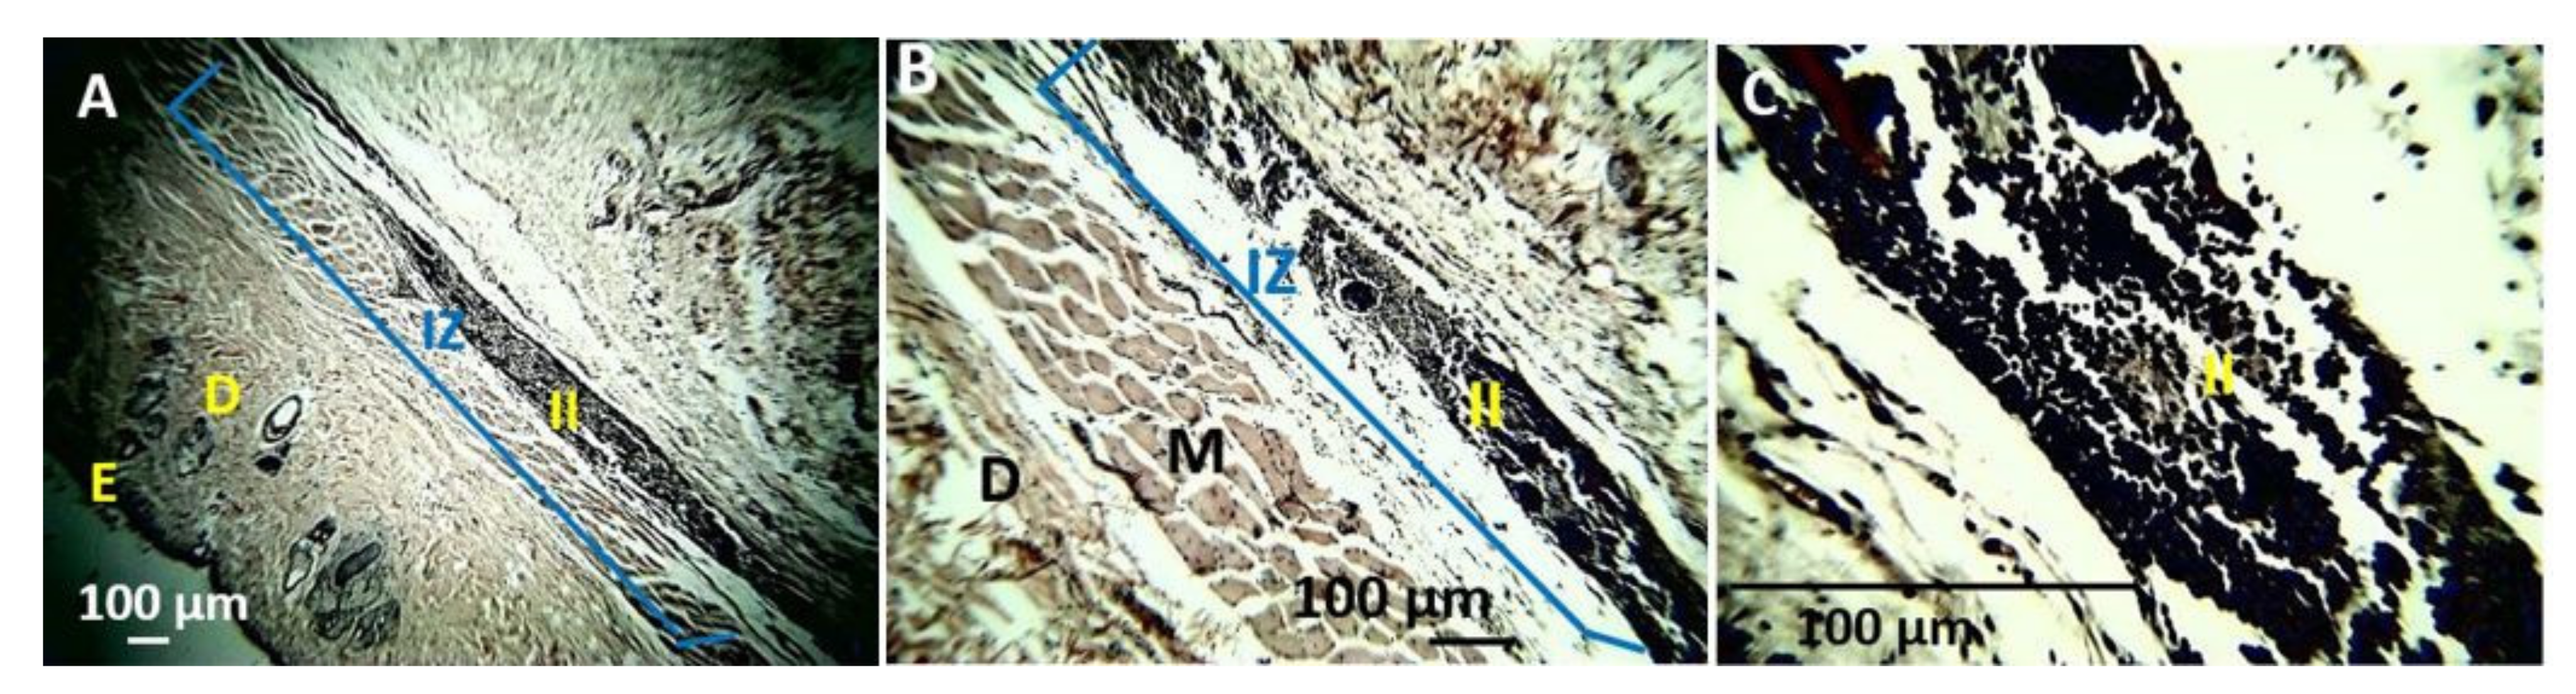

4. In Vivo Biocompatibility Tests of the CS/PVA/TTEO Films